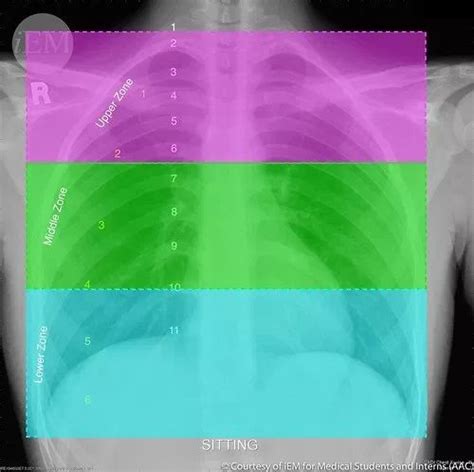

2. Lung Fields and Parenchyma

The lung fields should appear clear and dark on a normal chest X-ray, indicating the absence of consolidation or other pathologies. The lung parenchyma, which includes the alveoli, bronchioles, and capillaries, should not show any signs of disease such as opacities, nodules, or cavitations. The presence of any abnormalities in the lung fields can suggest a wide range of conditions, from infections to chronic diseases like emphysema. Thus, a thorough examination of the lung fields is essential for determining the normalcy of a chest X-ray.

3. Pleural Spaces and Costophrenic Angles

The pleural spaces, which are the areas between the lungs and the chest wall, should not contain any significant amount of fluid or air (other than what is considered normal). The costophrenic angles, where the diaphragm meets the rib cage, should be sharp and well-defined. Blunting of these angles can indicate pleural effusion, a condition where excess fluid accumulates in the pleural space, which can be a sign of various diseases, including infections, malignancies, and heart failure. A normal chest X-ray will show clear, unobstructed costophrenic angles.

4. Diaphragmatic Position and Movement

The diaphragm, the major muscle used for breathing, should be at an appropriate level and have a normal contour on a chest X-ray. The position of the diaphragm can be influenced by factors such as lung volume and gravity. In a normal inspiratory chest X-ray, the diaphragm should be at or below the 10th rib anteriorly and the 6th rib posteriorly. Abnormalities in diaphragmatic position or contour can suggest conditions affecting the lungs or the diaphragm itself. Moreover, assessing the movement of the diaphragm during breathing (through fluoroscopy or video X-ray) can provide additional insights into respiratory function.